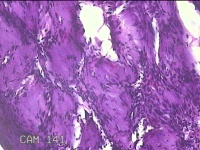

左示指肿物

性别

男

年龄

35岁

临床诊断

左示指末节肿物性质待查?

一般病史

发现左示指肿物

标本名称

大体所见

灰白暗红色肿物0.7x0.3x0.2cm一个,表面糜烂,切面灰白暗红色,质软。